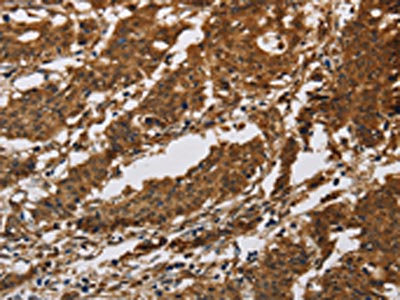

The image on the left is immunohistochemistry of paraffin-embedded Human gastric cancer tissue using CSB-PA891383(IL17RB Antibody) at dilution 1/40, on the right is treated with synthetic peptide. (Original magnification: ×200)